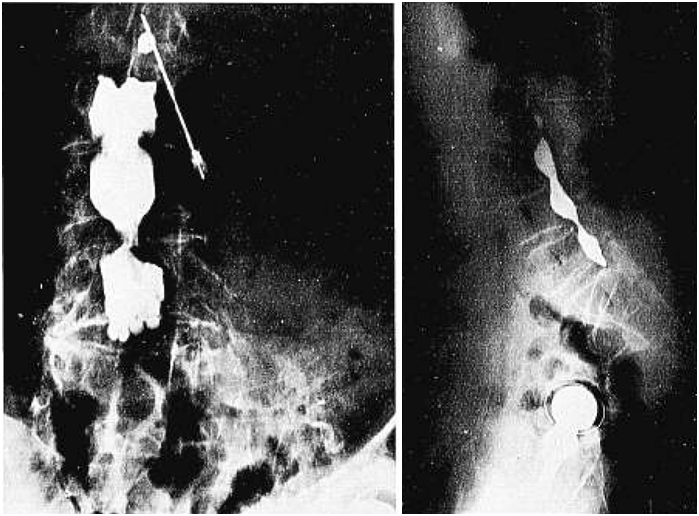

3. 继发型(Secondary,髋关节挛缩,图1和2)

- 僵硬平衡型(Rigid and balance, R/B型)

⁕ 长节段融合到骶骨

⁕ 坐位骨盆后旋受限

AA减少,髋屈曲受限,髋臼前损害,Hip后脱位

THA: AA 15-25°(较为安全)